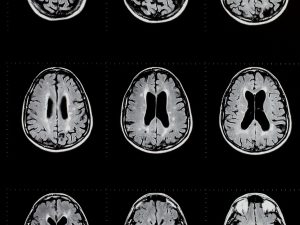

Brain tomography: Multiple Sclerosis Pain Management – treatment that may help.